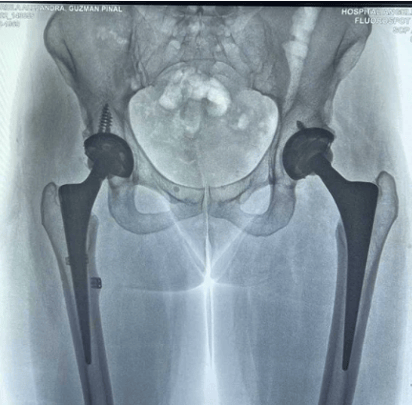

La cantante, que tiene dos prótesis en la cadera, y que desde el 2009 se ha sometido a múltiples cirugías para extraer de su cuerpo una sustancia llamada metil metacrilato, que le inyectaron cuando quiso aumentar el tamaño de sus glúteos, compartió con sus fans cómo luce su cadera tras el incidente en el escenario.

La cantante posteó la radiografía de su pelvis, donde se aprecian sus prótesis y escribió: "Todo en su lugar".